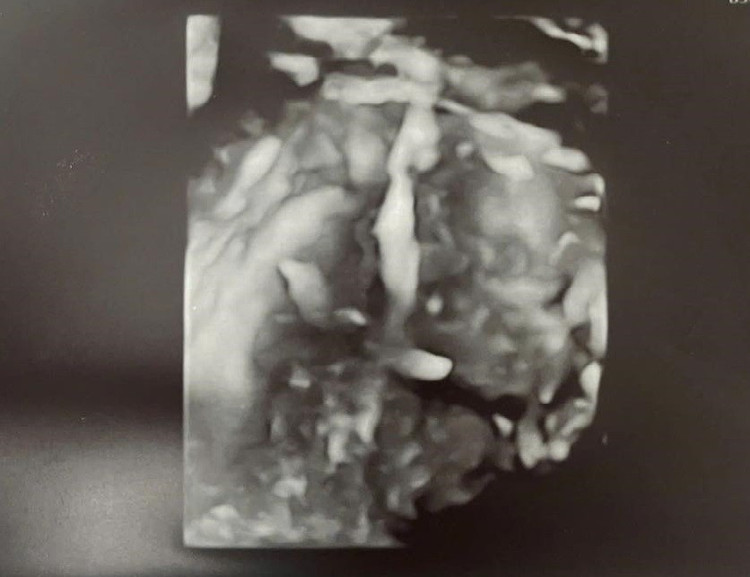

Hình ảnh vòng lạc chỗ trên phim chụp - Ảnh BVCC

Với sự phối hợp của Khoa Chẩn đoán hình ảnh và Khoa Gây mê hồi sức, bác sĩ Hiếu chỉ định sử dụng siêu âm 3D phụ khoa để dựng hình buồng tử cung chi tiết, xác định chính xác vị trí vòng đang nằm vùi trong lớp cơ, còn một phần nhỏ nằm trong buồng tử cung nhưng sát góc, một phần khác thì thò ra ngoài tử cung vào bụng (nhìn thấy phúc mạc đội lên), từ đó xây dựng phương án can thiệp tối ưu.